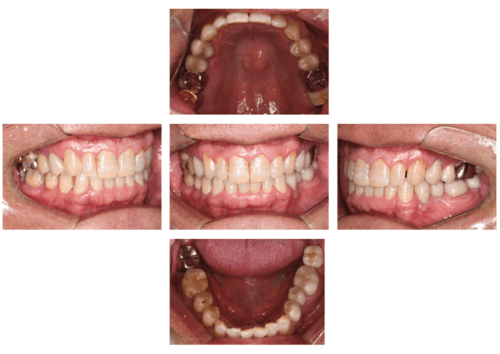

口腔内写真

- Befor

- After

| 年齢 | 50代・男性 |

|---|---|

| 主訴 | 左上7番 左下5番7番 |

| 治療内容 | ・インプラント埋入 ※1:GBR(骨造成)・・・骨再生誘導法。骨の高さや厚みを人工骨や人工膜などを使用し再生する方法 |

| 治療費 | 合計:1,809,500円(税込) ■内訳 ・左上7番 ・左下5番7番 |

| 治療期間 | 左上7番約1年 左下5番7番約10ヵ月 |

| 治療方針 | 左上7番は昔他院で被せものをしており、被せものの中が歯ぐきの中まで虫歯になっていたため抜歯せざるを得ない状態だった。抜歯と同時に骨造成を行い、骨が出来るまで4ヵ月待ってからインプラントを埋入した。 ※2ポンティック・・・歯のない部分を補うダミーの歯。 |

| 担当者所見 | 元々金属の被せものが多く入っていたため、2次カリエス※3が多かった。今回は金属ではなく、ジルコニアを使用し、2次カリエスにならないよう、患者様にはブラッシング指導とメンテナンスの重要性をお伝えした。 ※3二次カリエス・・・詰め物や被せものを入れた歯が虫歯になること。 |